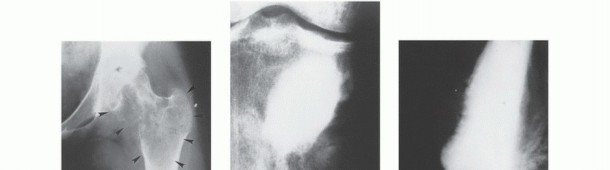

Mechanisms of Joint Involvement

Direct transarticular extension of a sarcoma through intact articular cartilage is exceedingly rare. When a joint is involved, it typically occurs via one of the following mechanisms:

1. Pathologic fracture extending into the intra-articular space, seeding the joint with tumor cells.

2. Pericapsular extension, where the soft tissue component of the tumor wraps around the joint capsule and invades the synovium.

3. Extension along intra-articular structures that insert directly into the bone (e.g., tumor tracking along the cruciate ligaments into the knee).

4. Transcapsular skip metastases (documented in ~1% of osteosarcomas).

- Plain Radiography: The cornerstone of initial evaluation. It accurately predicts the diagnosis in over 80% of extremity bone tumors. It defines the lesion's location, zone of transition (narrow/sclerotic = benign/slow; wide/permeative = malignant/aggressive), cortical destruction, and periosteal reactions (Codman triangle, onion-skinning, sunburst pattern).

- Computed Tomography (CT): The modality of choice for assessing fine osseous detail, cortical integrity, and matrix mineralization. Thin-slice (≤1 mm) helical CT allows for precise 3D reconstructions. Intravenous contrast is essential to delineate the relationship of the soft tissue mass to major vascular bundles. Chest CT is mandatory for staging to rule out pulmonary metastases.

- Magnetic Resonance Imaging (MRI): The gold standard for evaluating the local extent of the tumor. It accurately defines the intramedullary extent (allowing calculation of bone resection levels), soft tissue extension, joint involvement, and the presence of skip metastases. T1-weighted images best define marrow replacement; T2-weighted and STIR sequences highlight peritumoral edema and the soft tissue mass. Contrast enhancement differentiates cystic from solid components and clarifies neurovascular proximity.